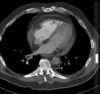

TC en TEP

Es diagnóstica, nos permite ver el trombo

95

TEP

96

4 = trombo

97